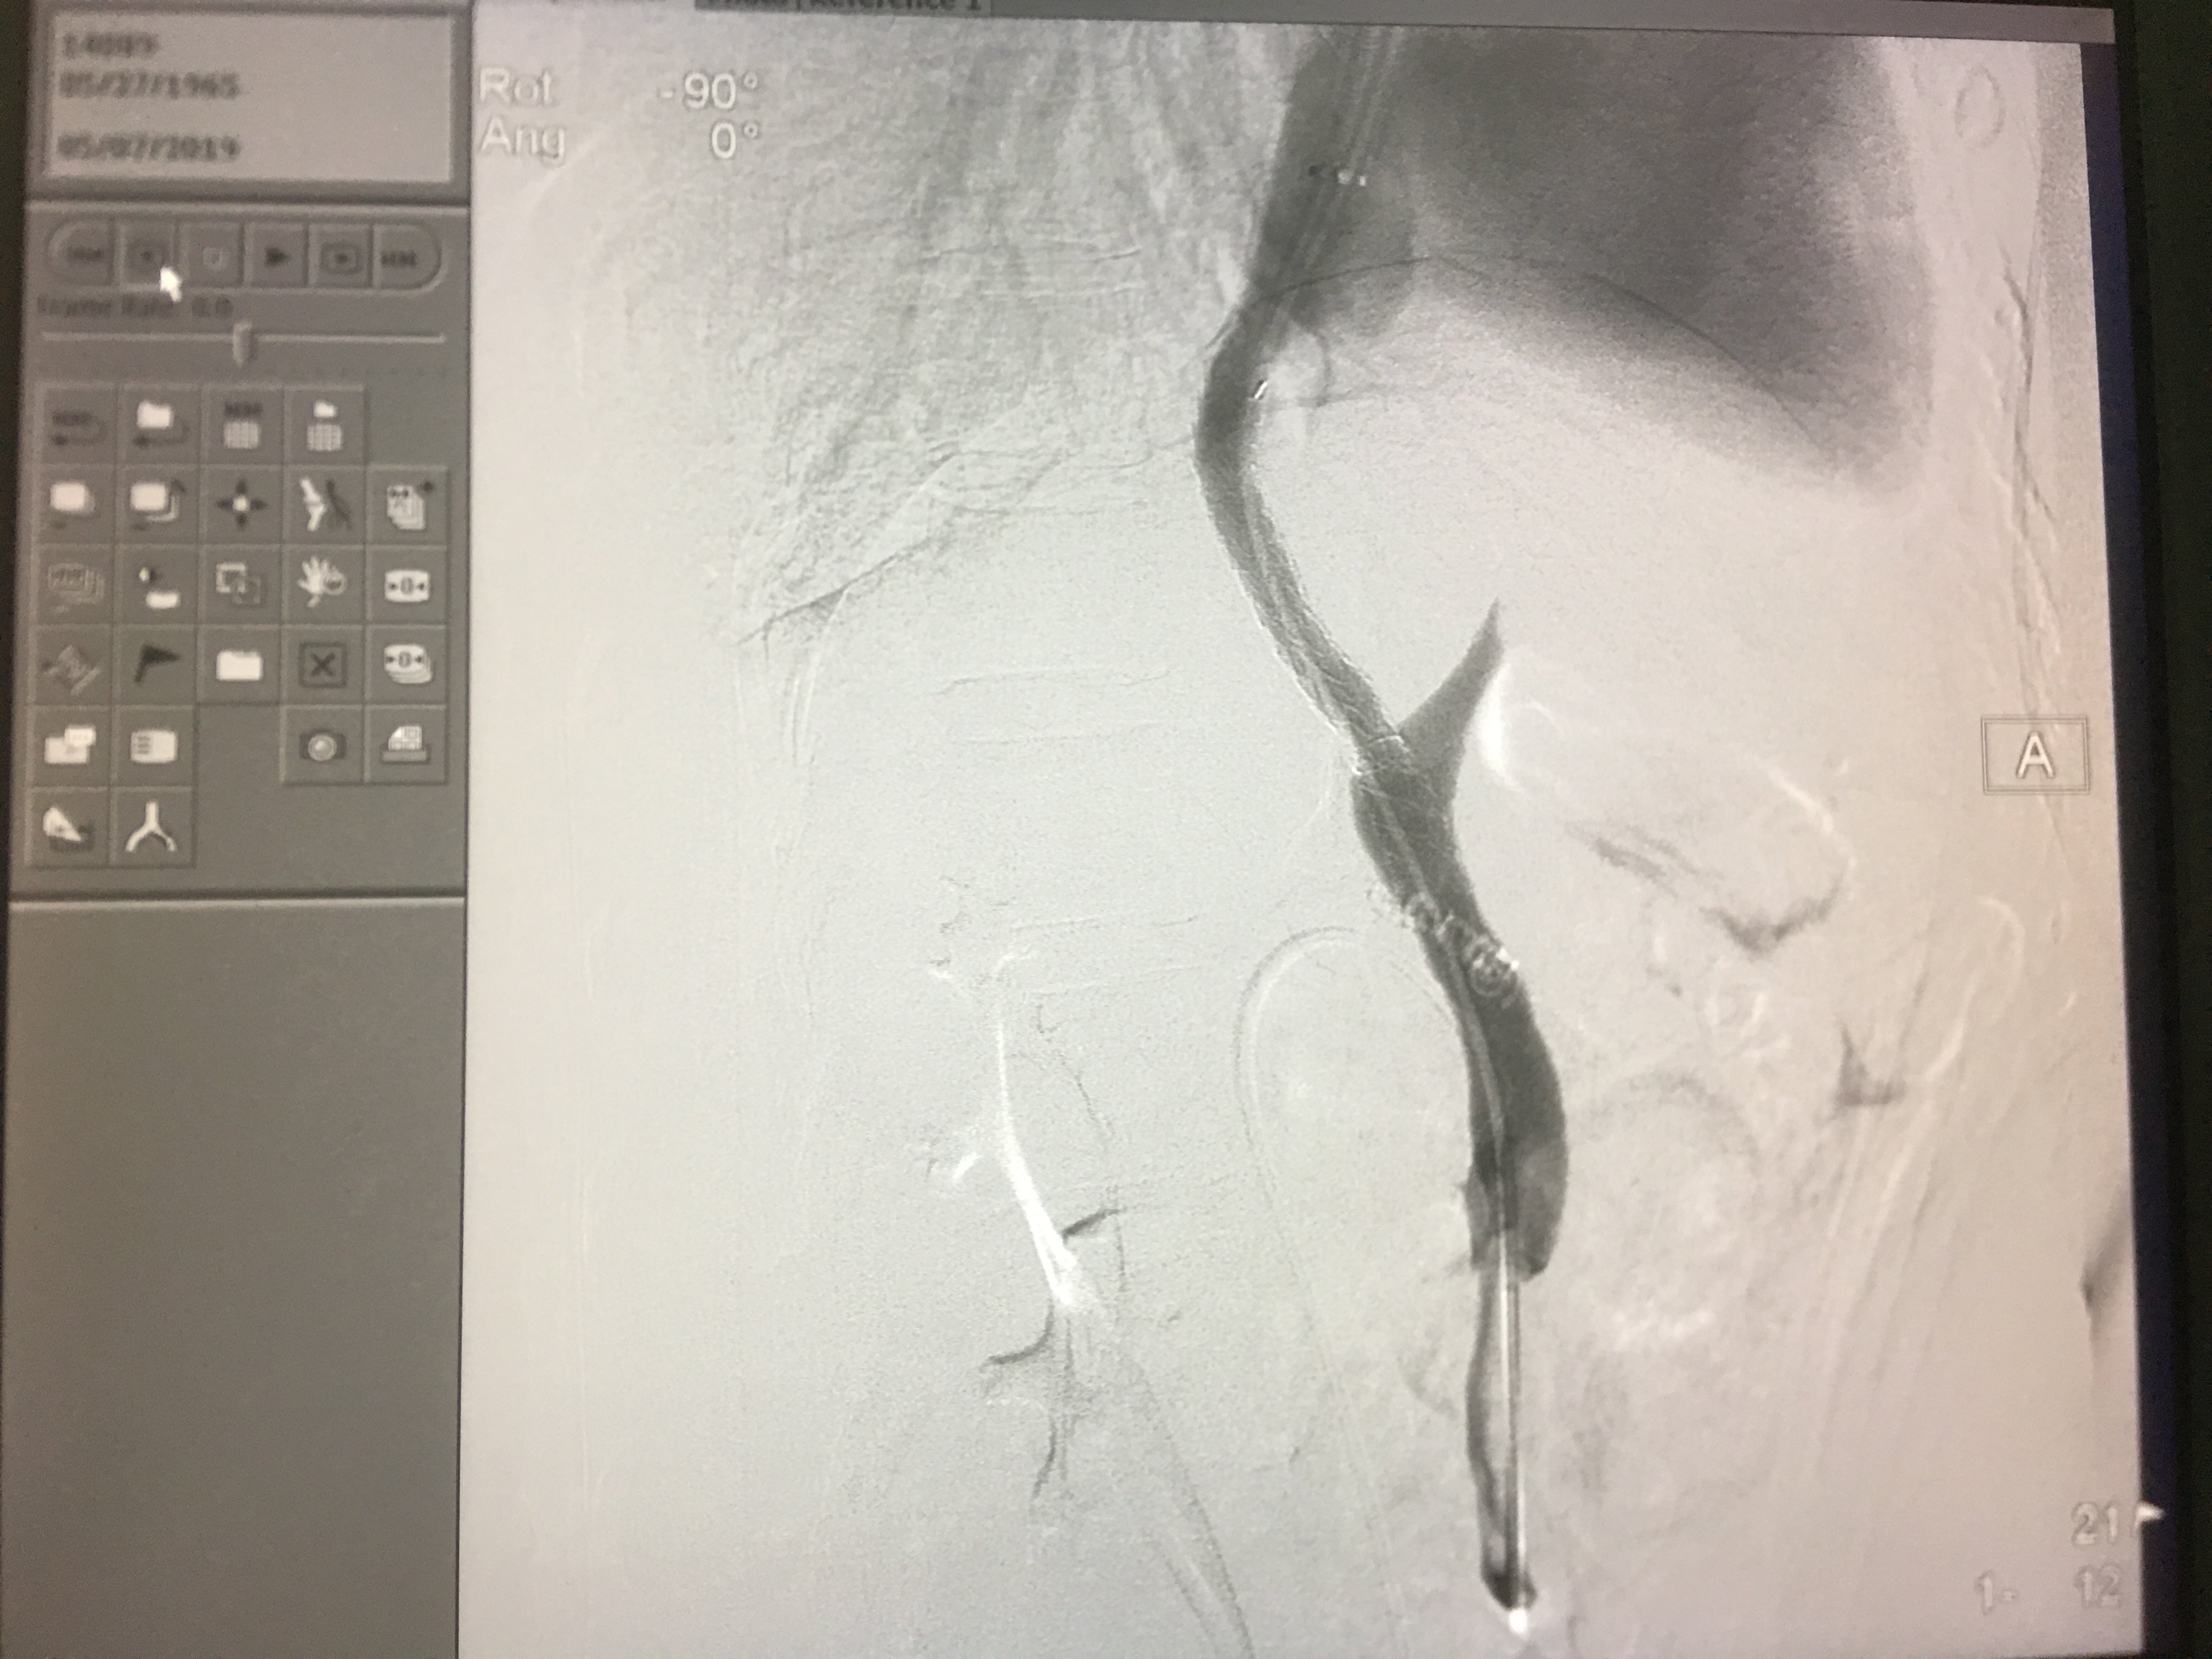

支架置入后再次造影并测压,压力下降明显。